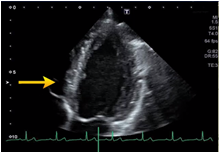

Adjustment of focus

Focus is the distance that provides the best resolution, usually set in the vicinity of the central part of the image. Set the focus point to match the part to be observed or the region of interest;in case you search for apical thrombus, set the focus point to the shallow part of the apical view.